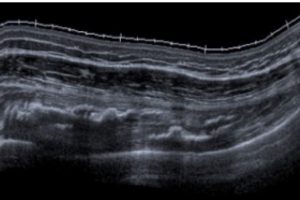

High frequency sound waves are able to travel freely through fluid and soft tissues. When these sound waves encounter a more solid surface such as cartilage, ligament, tendons and bone it is reflected back to the machine as an echo. When ultrasound encounters differing structures in the body it sends back echoes of varying strength depending on the density of the structures being scanned. These varying echoes are detected by the ultrasound probe and picked up by the machine, which in turn create an image of the soft tissue being scanned onto a monitor. An ultrasound scan is a very commonly used test and as it uses sound waves and not radiation it is considered to be very safe.

The ultrasound operator places a pen like probe on the skin over the part of your body to be examined. A water-based gel is also placed on the skin so that the probe makes good contact with your body. The probe is connected by a wire to the ultrasound machine, and linked to a monitor, allowing an image of the tissue to be displayed. The operator moves the probe around over the surface of the skin to obtain views of the tissues from different angles.